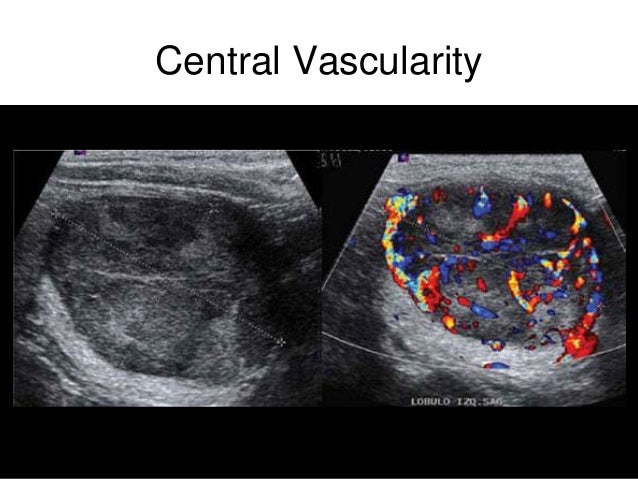

A physician carefully evaluates the thyroid and the cysts to determine how many there are and if the surrounding lymph nodes are abnormal which could indicate cancer. You can not tell if a thyroid nodule is malignant due to symptoms or lack of symptoms. The common treatments for thyroid cysts are.

Completely cystic thyroid nodules are unlikely to be cancerous. The cyst was over 43cm. Most thyroid nodules are benign non-cancerous but some thyroid nodules are thyroid cancer A small percentage of thyroid nodules are malignant cancer.

It seems like it is getting bigger every day. Ultrasound can help evaluate a thyroid nodule and. Most thyroid nodules are benign non-cancerous and cause no problems if left untreated.